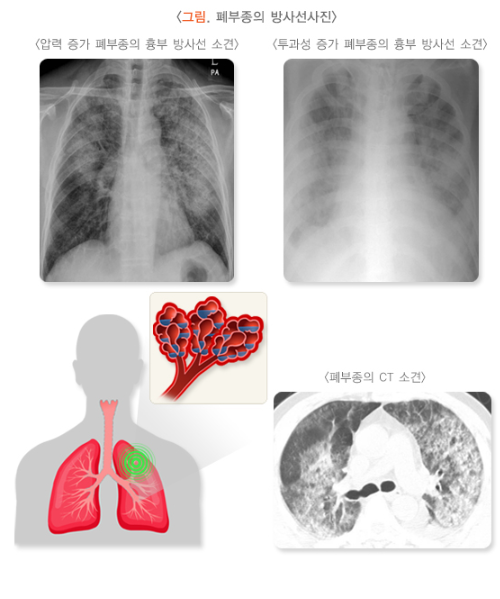

4. 흉부 엑스레이 (Chest X-ray)

- 흉부 엑스레이는 폐부종을 진단하는 데 매우 중요한 영상 검사입니다. 폐에 체액이 축적된 모습을 확인할 수 있으며, 폐부종이 있을 경우 일반적으로 폐에 흰색 음영(경화, 침윤)이 나타납니다.

- Kerley B선: 이는 폐부종에서 나타날 수 있는 특이적인 엑스레이 소견입니다. Kerley B선은 폐의 하부에 나타나는 수평선으로, 이는 폐에 액체가 축적되어 폐의 미세한 구조를 변화시킨 결과입니다.

- 심장 크기: 심장의 크기가 비정상적으로 커지거나 심장 우심방과 우심실의 비대가 관찰될 수 있습니다. 이는 심장성 폐부종에서 흔히 나타납니다.

5. CT (Computed Tomography)

- 흉부 CT는 폐부종을 더욱 세밀하게 평가할 수 있는 방법입니다. 엑스레이에서 확인되지 않는 미세한 변화나 폐의 추가적인 손상을 보여줄 수 있습니다.

- CT 스캔을 통해 폐에 축적된 체액, 폐의 염증, 폐렴이나 종양 등의 다른 원인 질환을 감별할 수 있습니다. 하지만 CT는 엑스레이보다 방사선 노출이 더 많으므로 필요 시 사용됩니다.